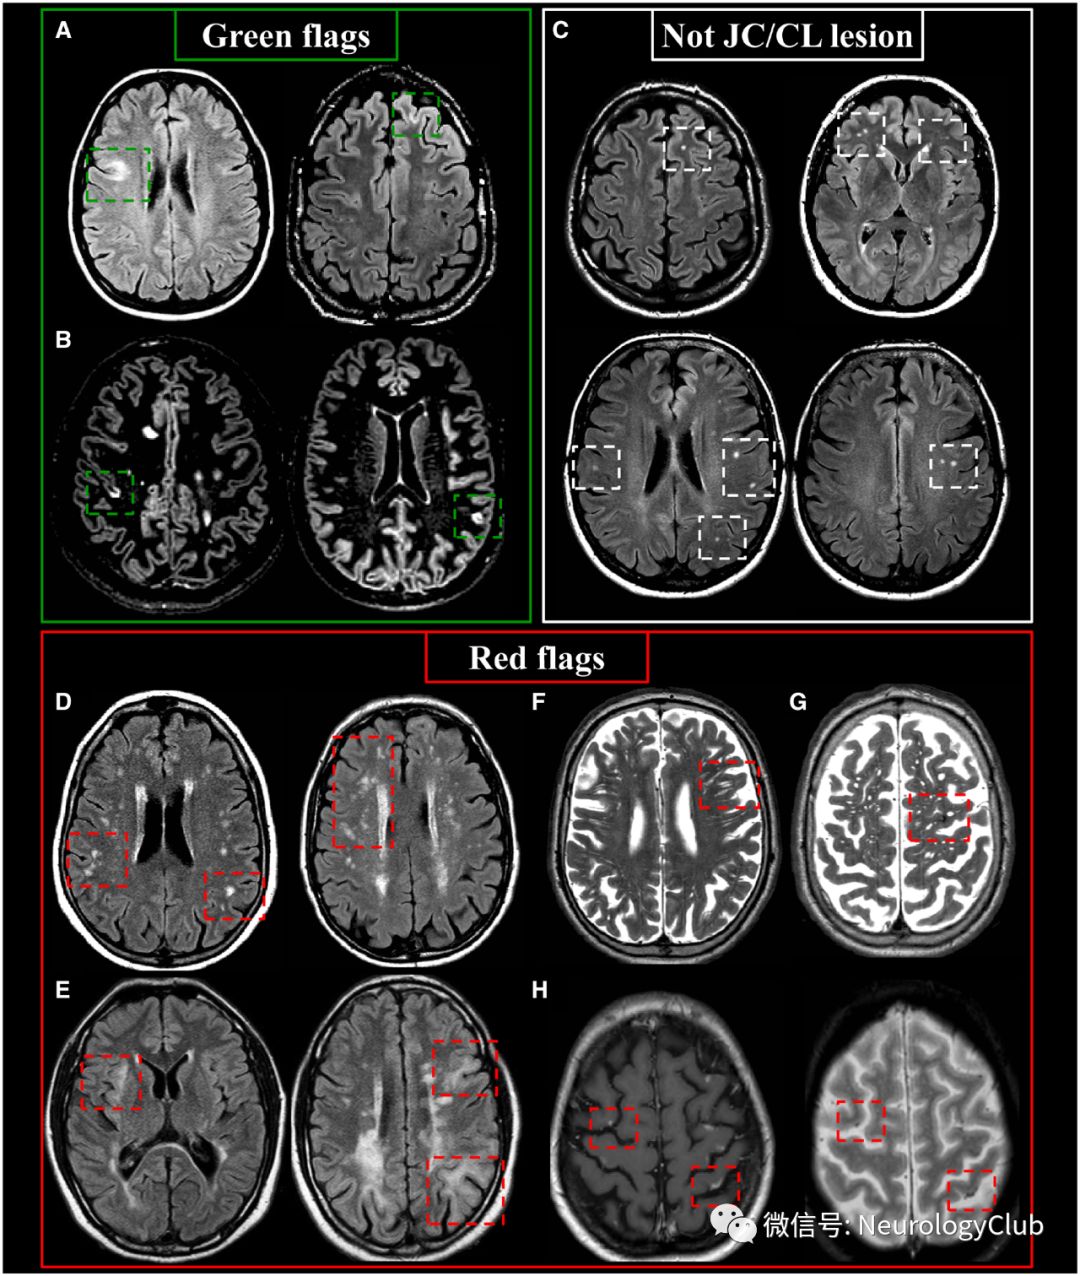

图3:MS患者幕下典型和非典型病灶;左:绿旗征:(A)幕下病灶;右:红旗征:(B)见于小血管病的对称性脑桥中央病灶;(C)NMOSD导水管周围病灶;(D)NMOSD极后区病灶;(E)MOG抗体相关疾病中脑-间脑病灶;(F)神经白塞病邻近四脑室底的大的卵圆形病灶